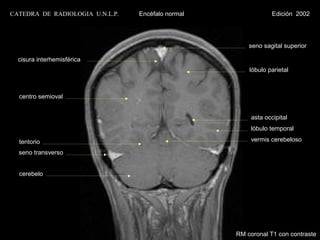

t.c.s.

circunvolución del

cuerpo c. calloso                                                  cuerpo calloso

rodilla c. calloso

rostrum c. calloso                                                  tálamo

tubérculos

espacio mamilopontino                         M                    cuadrigéminos

hipófisis                                                          tentorio

P                        IV ventrículo

seno esfenoidal

clivus                                                             cerebelo

B                amígdala

cerebelosa

agujero magno

médula cervical

M = mesencéfalo

P = protuberancia

B = bulbo

RM parasagital T1 con contraste